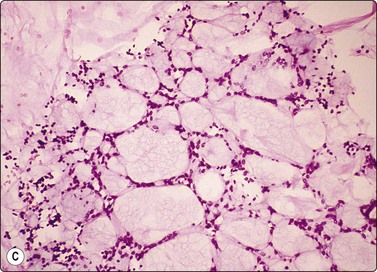

Other non-neoplastic lesions

Material aspirated from congenital bronchogenic cysts usually consists of mucin and bronchial-type epithelium unless infection supervenes. So-called ‘bronchoceles’, which represent recent-onset postinflammatory dilated mucin-filled bronchial structures, may yield similar findings, and correlation with clinical and sequential imaging findings is necessary for precise diagnosis. (Fig. 8.14).

image

Fig. 8.14 Bronchocele

Rounded mass in mid-lung field. Mucoid material aspirated at FNB. Smears show mucin, scattered macrophages and sheets of bronchial epithelial cells. Inset: Ciliated cells. Cytological findings consistent with either bronchogenic cyst or bronchocele. Recent onset of lesion more consistent with bronchcoele (H&E, HP; Inset, Pap, HP oil).